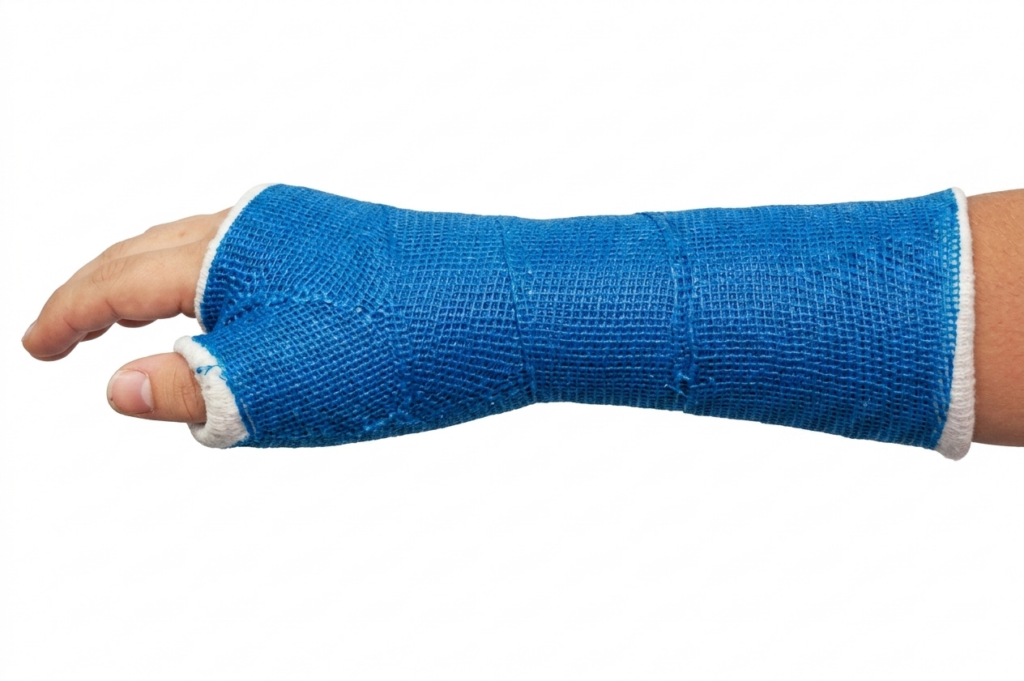

Many scaphoid fractures can be managed without surgery.

This typically involves:

- Immobilisation in a cast or splint

- Usually for 6–12 weeks, sometimes longer